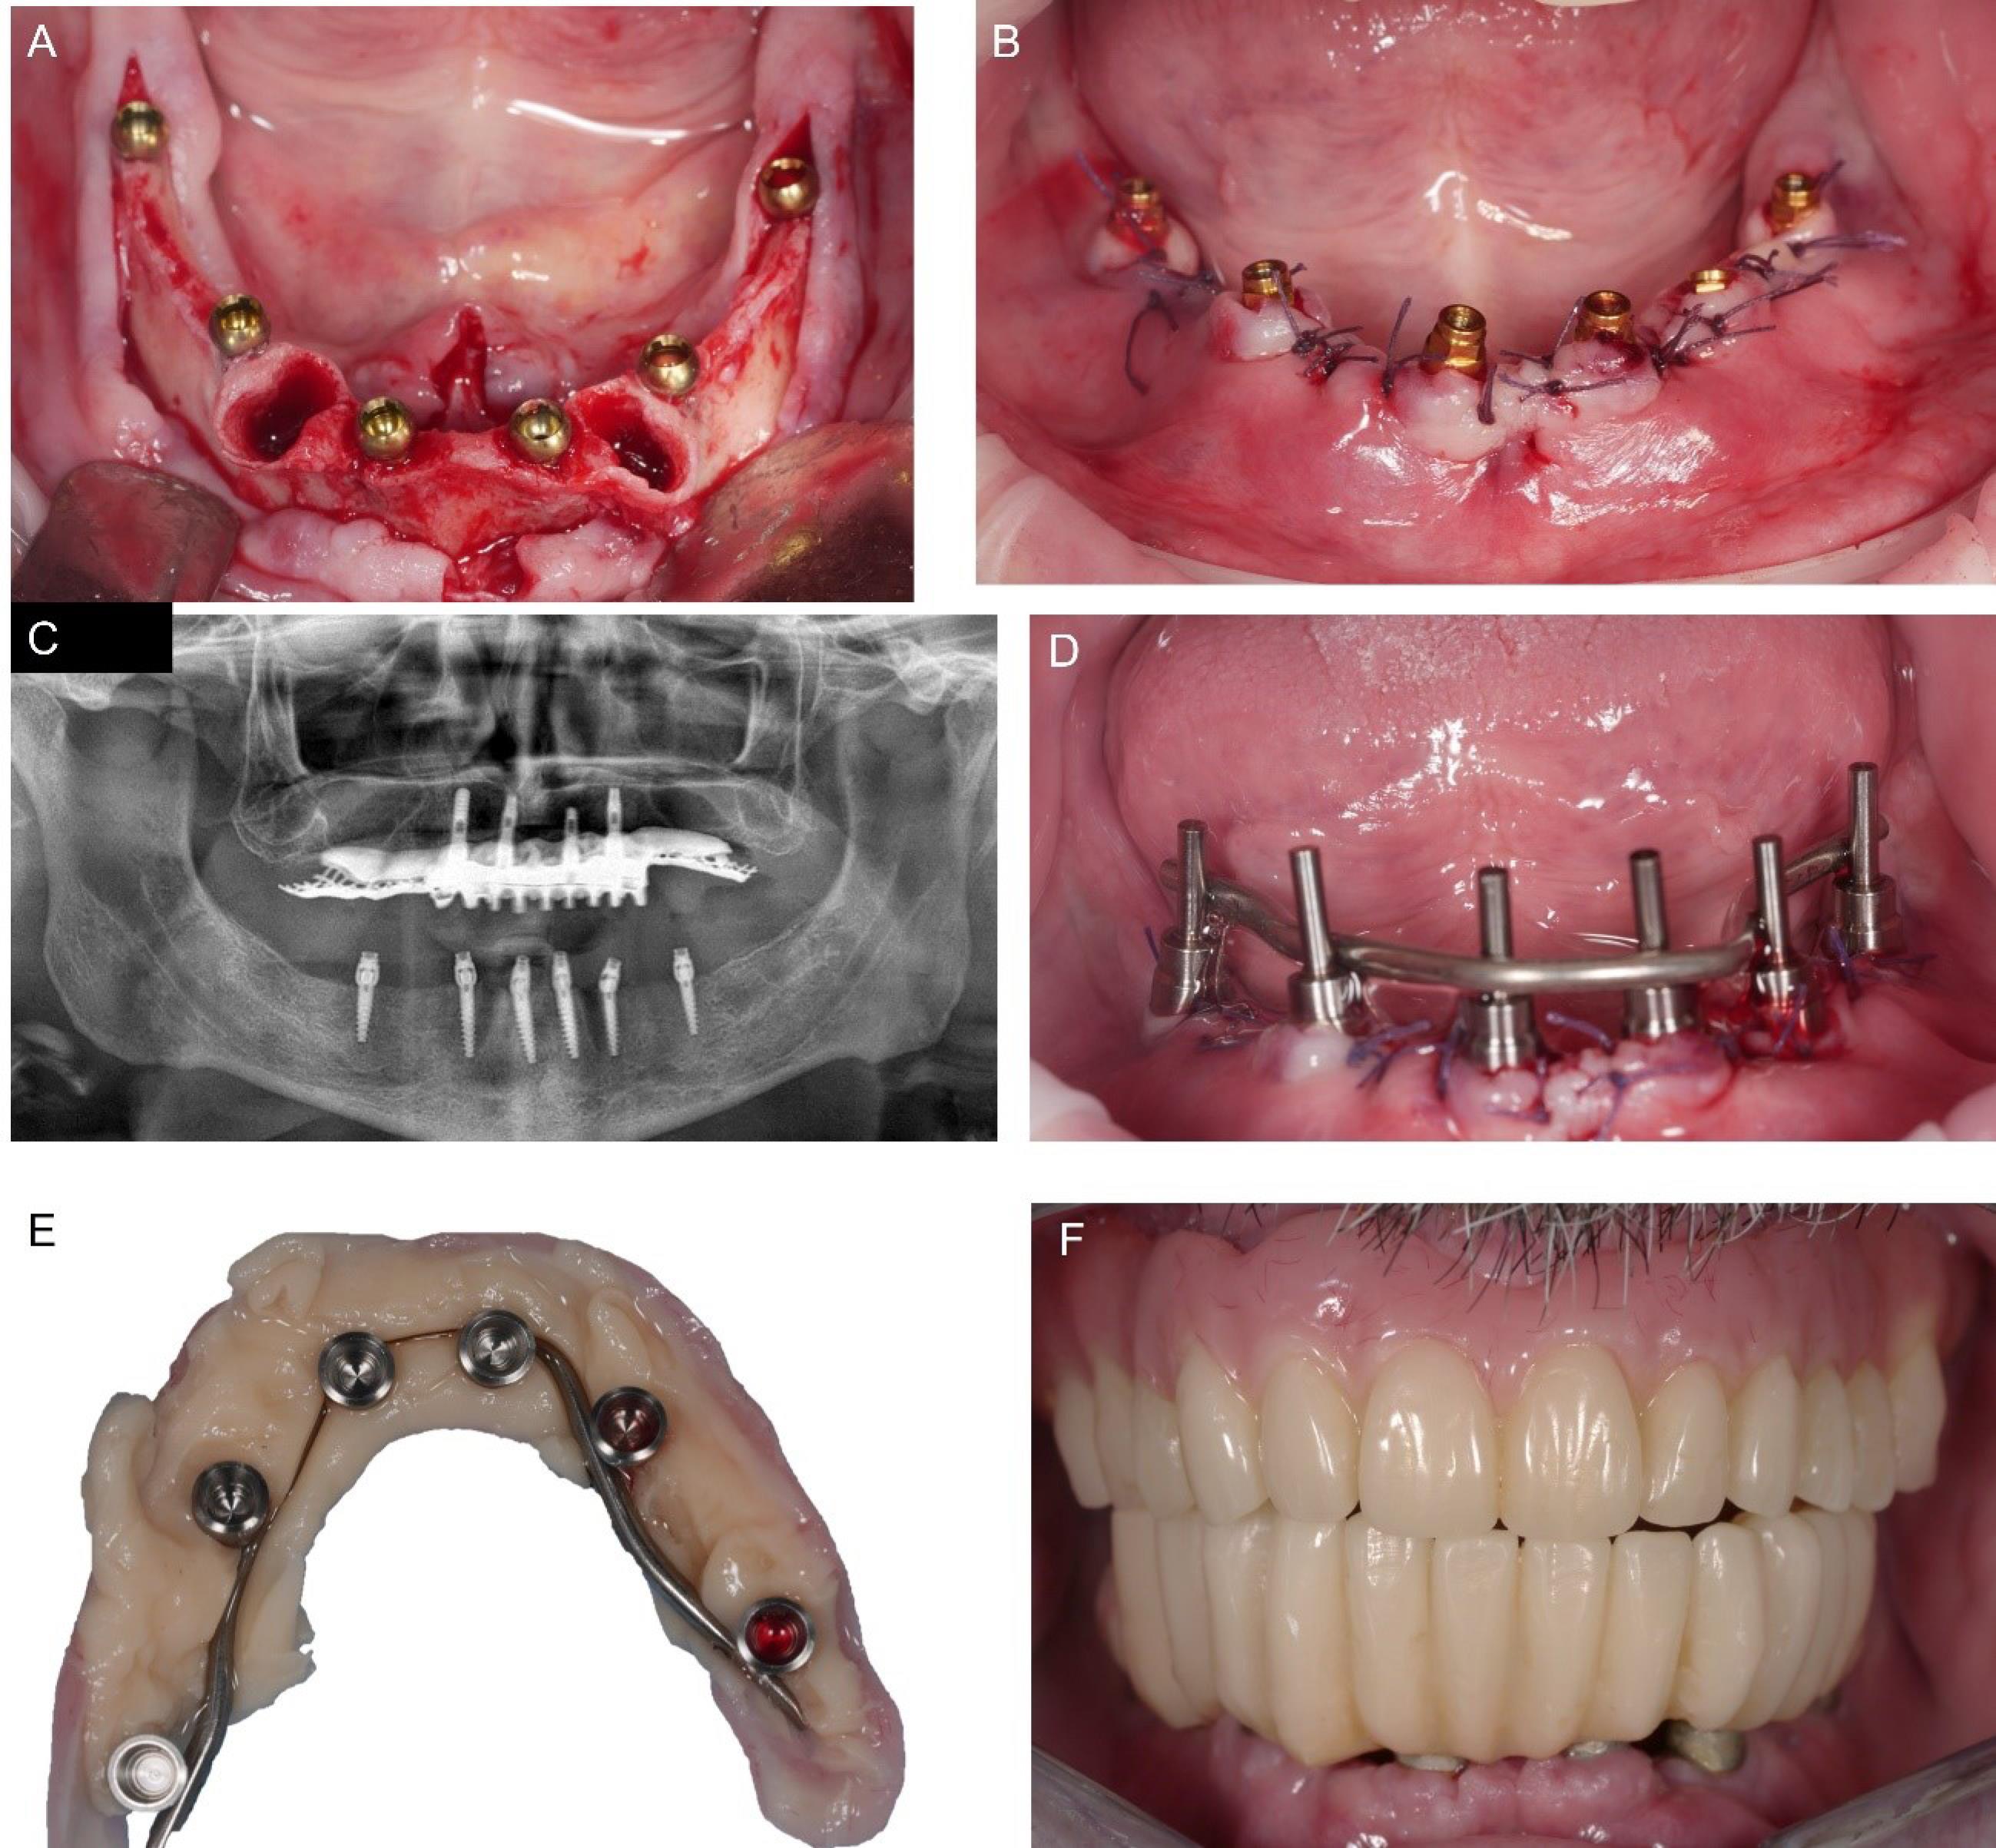

After a standard antibiotic prophylactic regimen (2 g of amoxicillin one hour before the procedure), a full-thickness flap with vestibular and lingual anterior releasing incisions was raised from the bone under local anesthesia. The cuspid dental roots were extracted, and six implants measuring 2.4 mm in diameter, Orbit (Bionica, Thiene (VI), Italy), were placed in 36/37, 34, 31/32, 41/42, 44, 46/47 correspondent tooth locations, all with the same length, 13 mm, apart from the rear ones, 11,5 mm (Figure 4A). The intermediate flat abutments, the LEMs, were snap-fit-connected to the fixtures’ heads, orientated parallel to each other, and blocked in the decided position turning the external ferrule screw, and the flap was sutured. (Figure 4B & 4C). The straight copings were connected with a frictional external Morse tapered joint to the intermediate abutments, intraorally welded together (Figure 4D), and enclosed in the provisional prosthetic structure, which was relined, refined (Figure 4E), and connected to the implants (Figure 4F).

Figure 4.

Intraoperative phases. Situation after the implant placement (A) and “LEM” connection (B). Panoramic x-ray to verify the correct implant position (C). Intraoral welding after the copings were matched (D). Mucosal surface of the provisional denture enclosing the copings (E) and intraoral placement (F)